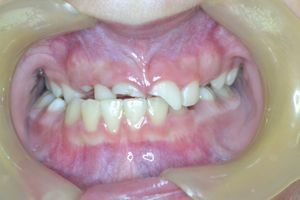

Το 9χρονο αυτό κοριτσάκι έσπασε τους κεντρικούς άνω τομείς μετά από πτώση στο έδαφος.

Τα δόντια απονευρώθηκαν και στη συνέχεια αποκαταστάθηκαν με συνδιασμό τοποθέτησης ενδοριζικών αξόνων και ανασυστάσεων σύνθετης ρητίνης.

Συγκεκριμένα, άξονες υαλονημάτων τελευταίας τεχνολογίας (ParaPost FiberWhite/Coltene και FiberCone/RTD) συγκολλήθηκαν εντός των ριζών και τα δόντια ανασυστήθηκαν με νανουβριδική σύνθετη ρητίνη (Herculite XVR Ultra/Kerr) με την βοήθεια ειδικής μήτρας/οδηγού από σιλικόνη.

Το χαμόγελο της μικρής ασθενούς μας αποκαταστάθηκε άμεσα όπως είναι εμφανές στην τελευταία φωτογραφία.